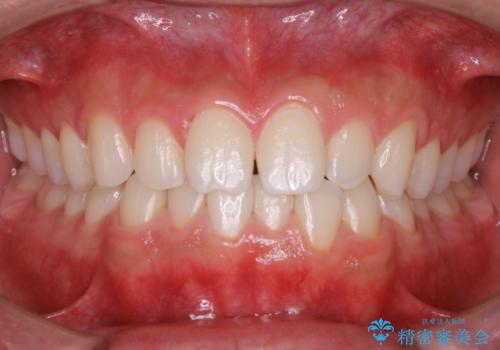

今回は、前歯メイン希望とのことでしたが、歯石やプラークが薄い付着だったため、30分コースの中で全体的クリーニングが行えました。

状態次第では、60コースでも全ての汚れが取り切れない場合もあります。